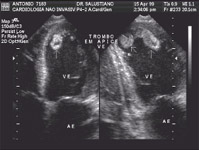

» Pesquisa de trombo intracavitário (situação particularmente importante na fibrilação atrial e estenose mitral).

» Pesquisa de vegetação na endocardite infecciosa.

» Pesquisa de fonte embólica por placa ateromatosa em aorta em pacientes com síndromes neurológicas e pesquisa de aneurismas dissecantes.

» Pesquisa de fonte embólica em geral, em pacientes com tromboembolismo periférico ou central.